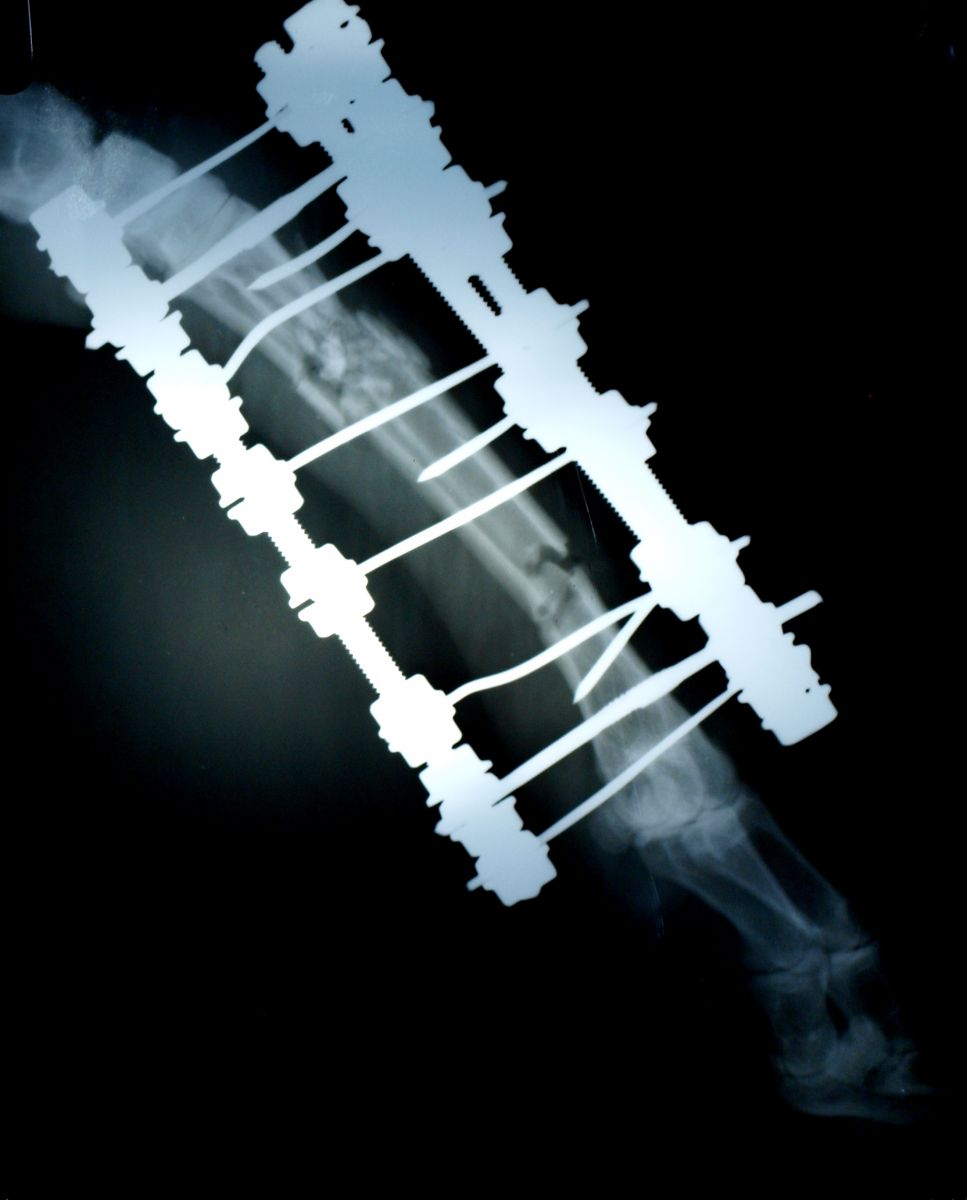

Использование аппарата наружной фиксации при лечении перелома у овцы

после наложения аппарата